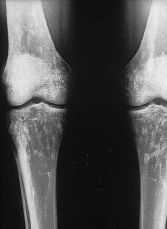

Para descartar una enfermedadsistematizada (por ejemplo, metástasis osteocondensantes) serealiza un estudio radiológico esquelético donde seencuentran imágenes similares de moteado irregular a nivelde muñecas y manos (fig. 2), pies (fig. 3), y rodillas (fig.4).

Figura4.